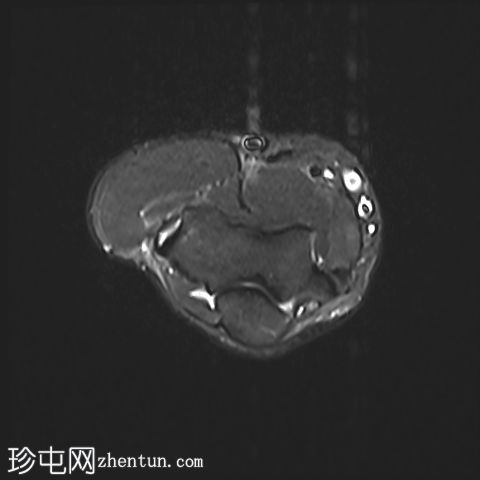

MRI

轴位

肘关节伸肌总腱增厚,腱内可见高信号及部分撕裂。伴周围软组织水肿。

本病例展现了网球肘的典型

学特征。